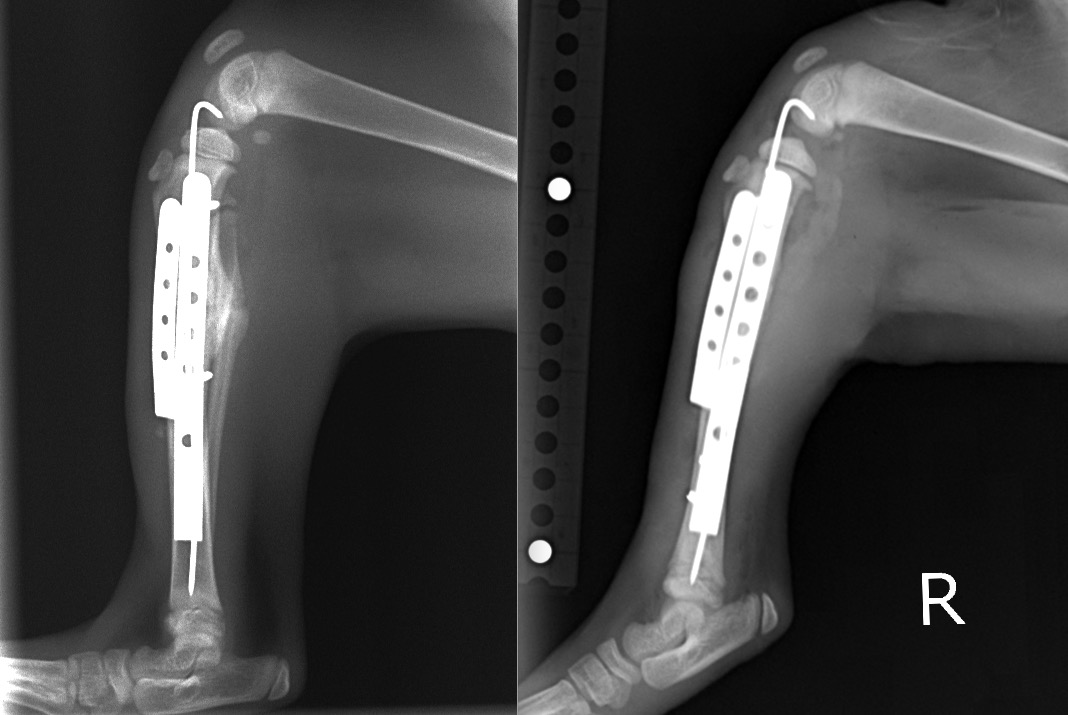

術直後、2週間後、4週間後のX線写真です。

若いゆえに治癒も早く、2週間でかなり骨の癒合が進み、4週間で骨折がほとんど治ってしまっています。

運動機能も問題なく、経過はとても良好と判断しています。

術後4週間/術直後